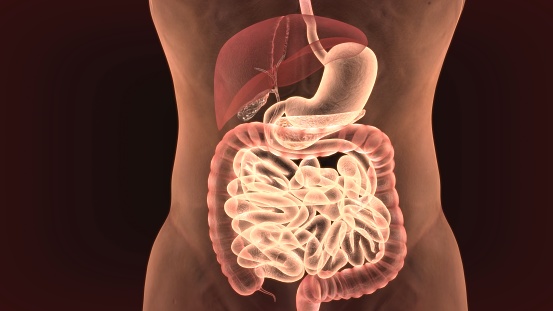

This one thing is worse than junk food for your digestion

We all know that eating unhealthily can leave our digestive system feeling not so good. Eating processed and sugary foods often leaves you bloated, gassy, and may even cause constipation and diarrhea. Aside from eating junk food, researchers have found that there is another factor that can harm our digestion equally as bad or even ...click here to read more